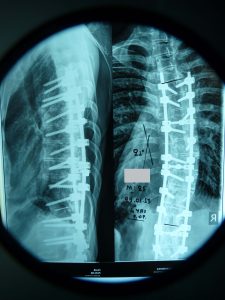

- α

- β

Εικόνα 5 (α,β) Μετεγχειρητική προσθιοπισθία και πλαγία ακτινογραφία.Παρατηρείται η σημαντικότατη διόρθωση του θωρακικού κυρτώματος παρά την εξαιρετικά μεγάλη δυσκαμψία αυτού, όπως είχε διαπιστωθεί στον προεγχειρητικό ακτινολογικό έλεγχο δια δυναμικών ακτινογραφιών καθώς και διεγχειρητικά. Το προεγχειρητικό θωρακικό κύρτωμα των 55ο μειώθηκε στις 25ο.